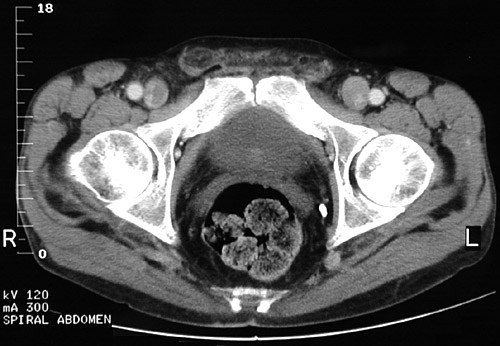

This pelvic CT scan demonstrates the normal appearance of

stool in the rectum

. The stool contains both air and solid components, giving it a textured appearance on CT scan. No bright contrast is present here.